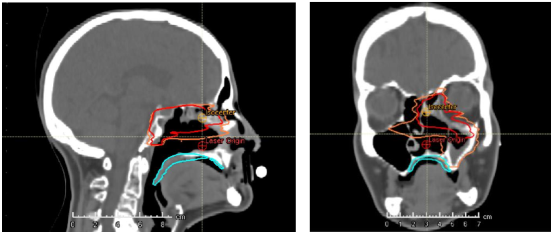

Strålebehandling mot hovud-halskreft kan for nokon pasientar medføra plagsame seneffekter som til dømes munntørrhet og svelgvanskar, noko som vil igjen vil ha ein negativ påverknad på pasienten sin livskvalitet. Strålebehandlinga for hovud-halskreft som vert tilbode i Noreg i dag er svært avansert og baserer seg på fotonstråling (røntgenstråling). Det finst òg andre teknikkar for strålebehandling som baserer seg på andre typar stråling, som protonterapi som i dag ikkje er tilgjengeleg i Noreg. Anlegg for protonterapi er likevel under bygging i Oslo og Bergen og ein planlegg å starte behandling av pasientar i 2024/2025. Ein antek at protonterapi kan vera nyttig for nokre pasientar med hovud-halskreft, først og fremst ved å redusera grad av plagsame seneffekter. Det er likevel enno uklart for kva for pasientar dette vil ha ein klinisk tyding. I dette prosjektet er føremålet å utvikla metodar og matematiske modellar som kan identifisera kva for pasientar som vil ha størst risiko for å få seneffekter etter strålebehandling. Pasientane vert inkludert i ein prospektiv studie der vi samlar kliniske og dosimetriske data, blant anna ved hjelp av spørjeskjema og måling av spyttsekresjon, både før pasienten startar behandling og fleire gonger i inntil  2 år etter behandling er avslutta. I tillegg vil ein nytta data om stråledose til ulike organ, og dessutan biletmaterial for å undersøkja korleis anatomiske endringar eventuelt kan påverka stråledosen. I framtida vil vi desse metodane og modellane kunne vert nytta for å velja ut kva for pasientar som blant anna bør tilbydast protonterapi. Studien er et samarbeid mellom Haukeland Universitetssjukehus og Oslo Universitetssykehus Radiumhospitalet.

En gruppe fargerike sko

Øvst kan ein sjå korleis stråledosen fordelar seg i pasienten med protonterapi, nedst kan en sjå korleis stråledosen fordelar seg med fotonterapi